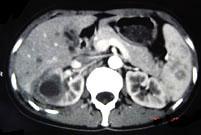

问题 女,33岁,右胁腹痛7天,尿检可见大量的脓细胞,CT平扫+增强如图所示,下列说法正确的是 ( )

选项 A、考虑为右肾囊肿合并感染 B、考虑为右肾脓肿 C、增强扫描可见该病灶不均匀强化,其内有无强化的坏死灶 D、右肾病灶边界模糊不清 E、右肾体积增大,其内可见类圆形低密度病灶

答案 BCDE